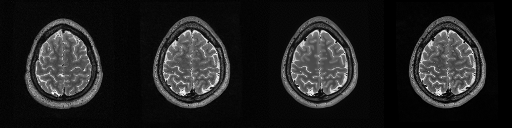

HCP T2w dataset

We utilize images from the publicly available Human Connectome Project (HCP) [51] T2-weighted (T2w) images dataset for the task of compressed sensing, which contains brain images from 47 patients. The HCP dataset includes cross-sectional images of the brain taken at different levels and angles.

Compressed sensing

We train a flow-based model from scratch on 10,000 randomly sampled images, utilizing the ncsnpp architecture [9] with minor adaptations for grayscale images. We employ compression rates , meaning . The measurement operator is given by a subsampled Fourier matrix, whose sign patterns are randomly selected. We evaluate our reconstruction algorithm’s performance on 200 randomly sampled test images.

We present the quantitative and qualitative results of compressed sensing in Tab. 1 and Fig. 4, respectively. As shown in Tab. 1, our method consistently achieves the best performance across varying compression rates . In Fig. 4, our method produces reconstructions that are more faithful to the original images, with fewer artifacts, leading to higher accuracy and clearer details.